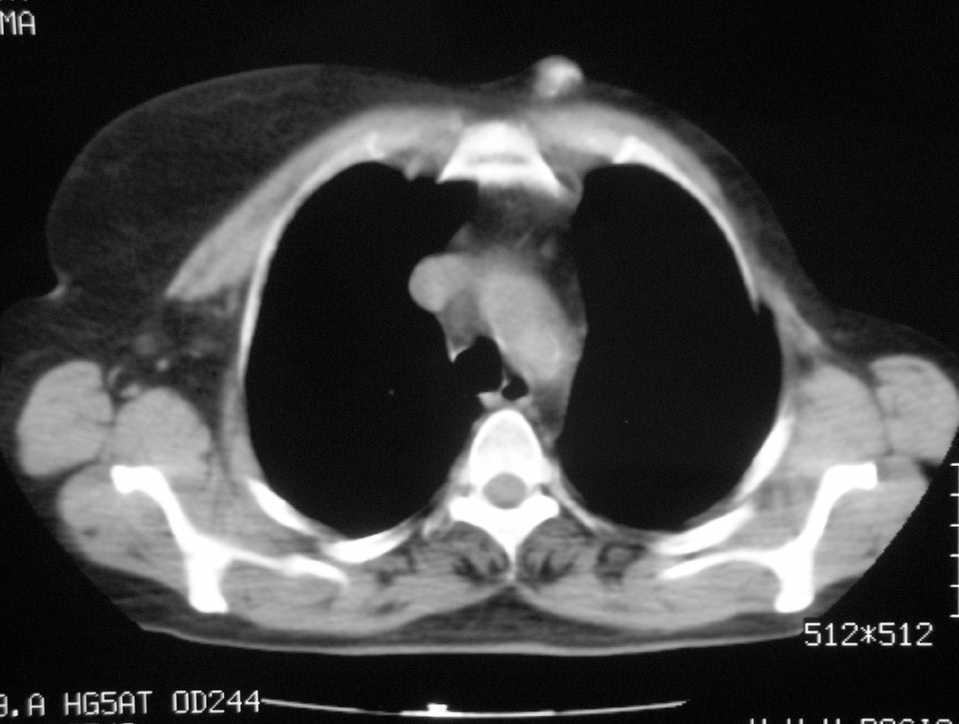

Paciente de 60 años de edad, con el antecedente quirúrgico de mastectomía radical modificada según la técnica de Patey en el año 1994, diagnosticada de carcinoma ductal infiltrante de 2,1 cm de diámetro, con 7 de 18 ganglios afectados, el 75% de receptores estrogénicos. Tras la intervención se somete a poliquimioterapia con protocolo secuencial 4-epirrubicina y CMF (ciclofosfamida, metrotexato y 5-fluorouracilo) y a sesiones de radioterapia (dosis total administrada de 50 Gy, 2 Gy por sesión). Continúa durante 5 años en tratamiento con tamoxifeno. Acude a la consulta de patología mamaria, derivada por el servicio de oncología, por presentar un nódulo paraesternal izquierdo, adherido a los planos profundos, de reciente aparición, que ha crecido hasta alcanzar los 2 cm de diámetro. Se aporta estudio mediante tomografía computarizada (fig. 1), donde cabe destacar la descripción de un nódulo parcialmente calcificado en el tejido celular subcutáneo, por delante del comienzo del manubrio esternal, en su lado izquierdo, que no parece relacionarse con los planos musculares. En la gammagrafia ósea aparece un aumento de captación del trazador (99mTC) muy bien delimitada en la parte izquierda de la unión del manubrio con el cuerpo esternal. La ecografía de partes blandas realizada informa de la presencia de un nódulo de 17 mm, subcutáneo, situado por encima del músculo pectoral, con zonas alternantes hiperecogénicas e hipoecogénicas, no vascularizado.

Figura 1. Tomografía computarizada de tórax. Nódulo paraesternal izquierdo por encima del músculo pectoral.